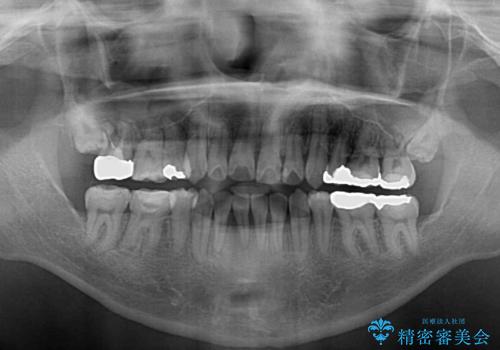

- 上下の八重歯やデコボコを気にして来院された患者様です。

上下ともに八重歯が顕著であったので、上下左右第一小臼歯4本を抜歯し、ワイヤー装置にて矯正治療を行うこととしました。

デコボコが強いことが原因で歯間部に汚れが溜まりやすい状態でしたが、矯正前にできる限り汚れが少なくなるようにブラッシングなどの指導を行い、口腔状態が改善された後にワイヤー装置を装着することとしました。